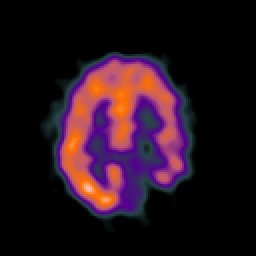

SPECT TC Study #6 -- Slice #38

[Home][Help][Clinical][Tour 1][Tour 2][Tour 3] Slice 38